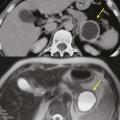

Tumeur kystique mucineuse

Les tumeurs kystiques mucineuses (TKM) sont des lésions précancéreuses bordées par un revêtement épithélial, sécrétant de la mucine. Il est caractéristique de trouver un stroma de type ovarien, positif en immunohistochimie à la progestérone. Le sex-ratio est fortement en faveur des femmes  : (20 femmes pour 1 homme). La découverte est principalement fortuite ou plus rarement sur pancréatite aiguë. Il s’agit d’une lésion unique, macrokystique, sans communication avec les canaux pancréatiques. Elle se situe quasi exclusivement au niveau de la face postérieure du corps et de la queue du pancréas (fig. 3). La lésion est uni- ou multiloculaire, limitée, hypodense, avec rehaussement de la paroi. Il existe de possibles nodules muraux, calcifications périphériques ou cloisons internes.

Le taux de risque d’évolution vers un cancer est inconnu. Les critères comme une taille supérieure à 7 cm, une épaisseur des septas et de la paroi supérieure à 3 mm, un nombre de kystes supérieur à quatre, la présence de nodules, un contenu liquidien hyperintense en séquences IRM T1, une compression ou infiltration périlésionnelle sont associés à des critères de dégénérescence en cystadénocarcinome.11